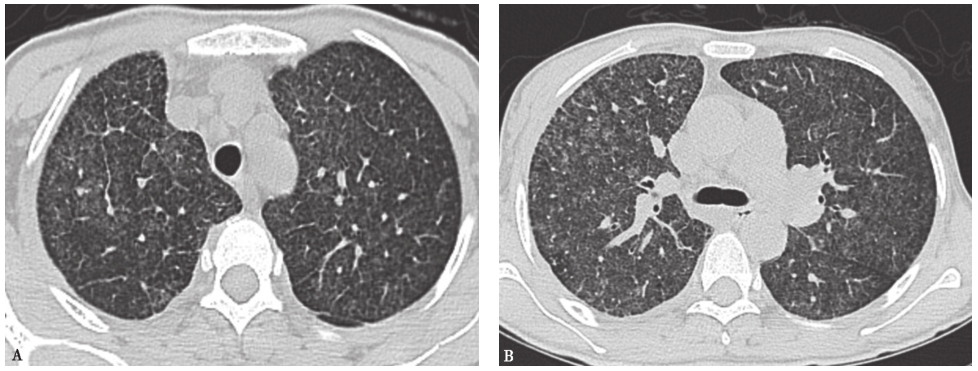

可出现类似胸部CT表现的感染性疾病有血行播散型肺结核、血行播散性真菌感染。血行播散型肺结核急性期胸部CT可见两肺大小、密度、分布“三均匀”的粟粒样结节,多数结节直径<3mm,边缘一般清楚(图3),一般不引起近肺门部的支气管血管束结节;亚急性期则表现为结节大小、分布、密度多不均一,中上肺野多见(图4),部分病灶可融合并产生干酪样坏死、空洞形成。多数患者有结核分枝杆菌感染中毒症状,痰检可发现结核分枝杆菌,结核菌素试验呈强阳性,红细胞沉降率增快等。本例患者无典型结核分枝杆菌感染中毒症状,痰抗酸杆菌阴性,正规抗结核治疗1年余,症状、影像学均无明显改善,故结核分枝杆菌感染可能性不大。

图3粟粒性肺结核胸部CT表现

女性患者,39岁,发热伴胸闷1个月余,病理诊断为粟粒性肺结核。胸部CT可见双肺随机分布的弥漫粟粒性结节

图4肺结核胸部CT表现

女性患者,76岁,反复发热2个月,伴发认知障碍3天,诊断为肺结核、结核性脑膜炎。胸部CT可见双肺分布不均、大小不等的多发结节影